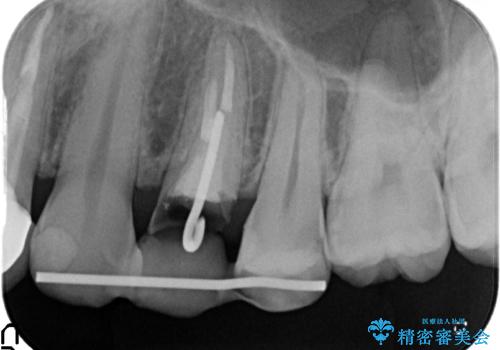

左上4の補綴物を除去したところ縁下歯質だったため、歯牙の挺出を提案し行いました。

挺出終了後は歯肉切除および骨外科により歯周組織を整え、オールセラミッククラウンによる補綴を行いました。